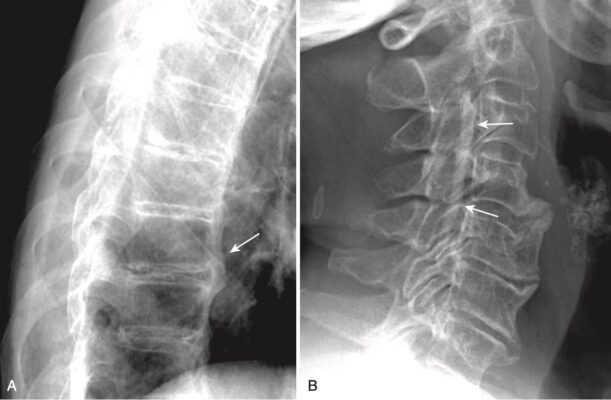

- Ở cột sống cổ, các gai xương ở các khớp mỏm móc đốt sống có thể tạo ra các lồi xương vào trong các lỗ ghép thần kinh hình bầu dục bình thường, có thể thấy được trên phim X quang thường quy chụp chếch (Hình 8, A).

- Thường có một mối liên hệ phức tạp giữa bệnh thoái hóa đĩa đệm và thoái hoá khớp liên mỏm facet và hai bệnh này thường cùng xảy ra. Các gai xương do thoái hoá khớp liên mỏm cũng có thể xâm lấn vào lỗ ghép thần kinh và gây đau rễ.

- Ở cột sống thắt lưng, thoái hóa khớp diện nhỏ có thể gây hẹp và đặc xương các khớp diện nhỏ, thấy rõ nhất với hình chụp chếch. Thoái hoá khớp diện nhỏ dễ nhìn thấy hơn trên phim chụp CT cột sống so với chụp X quang thường quy, và chèn ép dây thần kinh thực sự dễ nhìn thấy hơn trên MRI cột sống (xem Hình 8, B).

- DISH được biểu hiện bằng sự vôi hóa/cốt hoá dày, bắc cầu của dây chằng dọc trước hoặc đôi khi là dây chằng dọc sau (Hình 9).

- Sự cốt hoá này được thấy dọc theo mặt trước hoặc mặt trước của ít nhất bốn thân đốt sống liền kề. Không giống như bệnh thoái hóa đĩa đệm, khoang đĩa đệm và các khớp diện nhỏ (thường) được bảo tồn. Cốt hoá bắt cầu trong DISH hơi tách ra khỏi thân đốt sống (xem Hình 9, A).

- Cốt hoá dây chằng dọc sau (Ossification of the posterior longitudinal ligament, OPLL) thường xuất hiện với DISH và được nhìn thấy rõ hơn trên CT và MRI. Tình trạng này có thể gây chèn ép tủy sống, đặc biệt là ở cột sống cổ, do ống sống bị thu hẹp (xem Hình 9, B).